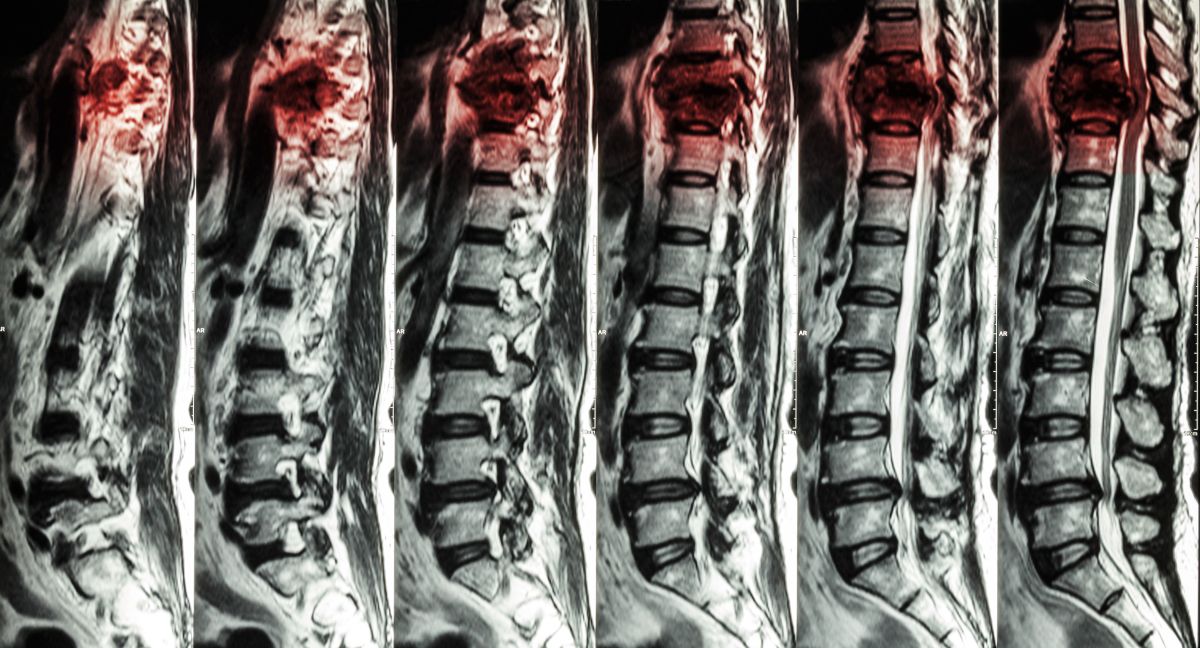

Lesión medular

Varios estudios científicos publicados a lo largo de 2025 analizaron nuevas estrategias terapéuticas dirigidas a la regeneración de la médula espinal tras una lesión medular, una de las principales causas de paraplejia, mediante enfoques que incluyen fármacos, activación de células madre internas y trasplantes celulares en fases experimentales y clínicas, según la información facilitada por el grupo de información científica 'Nature'.